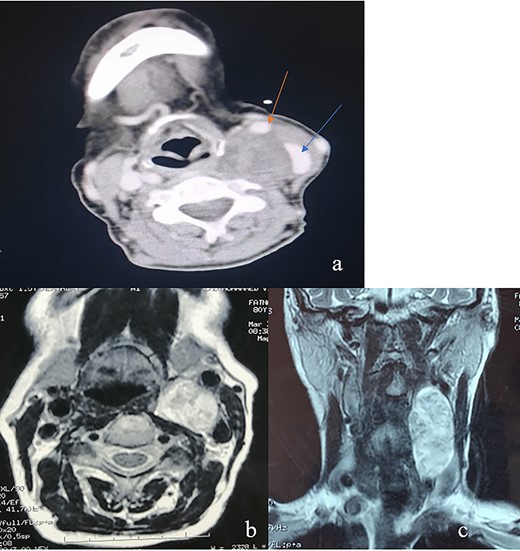

Computed tomography (CT) scan of the neck described a left neck mass (3.7, 3, 5.7 cm), hypodense, heterogeneous and not enhanced after injection of the contrast product. The mass displaced the common carotid artery (CCA), the external carotid artery (ECA) as well as the internal carotid artery (ICA) anteriorly and the internal jugular vein (IJV) anterolaterally. Magnetic resonance imaging (MRI) showed a low signal intensity T1-weighted and a high signal intensity T2-weighted mass (Fig. 1). These radiological findings aligned most closely with a diagnosis of vagal nerve schwannoma (VNS), therefore cervical sympathetic chain schwannoma (CSCS) could not be excluded.

(a) An axial CT of the neck revealing an oval heterogeneous mass in the left carotid space measuring 37 × 30 × 57 mm; the IJV (blue arrow) is displaced laterally and the CCA (red arrow) is displaced anteriorly; this is often a characteristic sign of VNS; (b) an axial T2-weighted MRI; left carotid space mass, noninfiltrating widening the space between CCE and IJV; (c) an coronal T2-weighted MRI showing a left carotid space mass with vertical major axis.